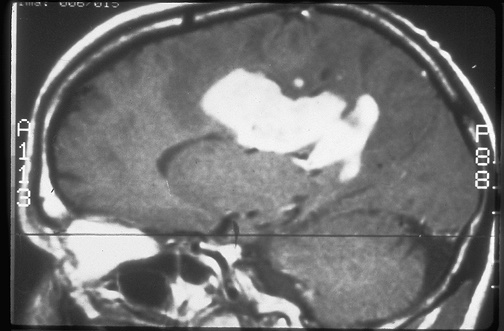

Image 6.1

This is an enhanced MRI scan of the right hemisphere as seen sagittally. [Image contributed by Jeannette J. Townsend, MD, University of Utah]